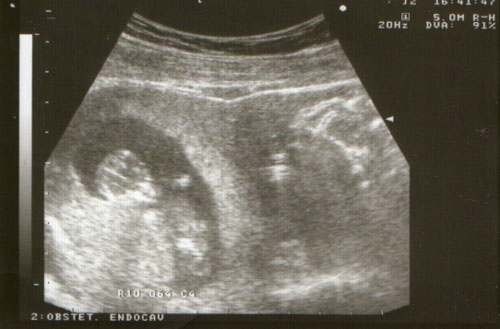

Várjuk a uh képet. Tényleg nagyon cuki a kislányod a képen.